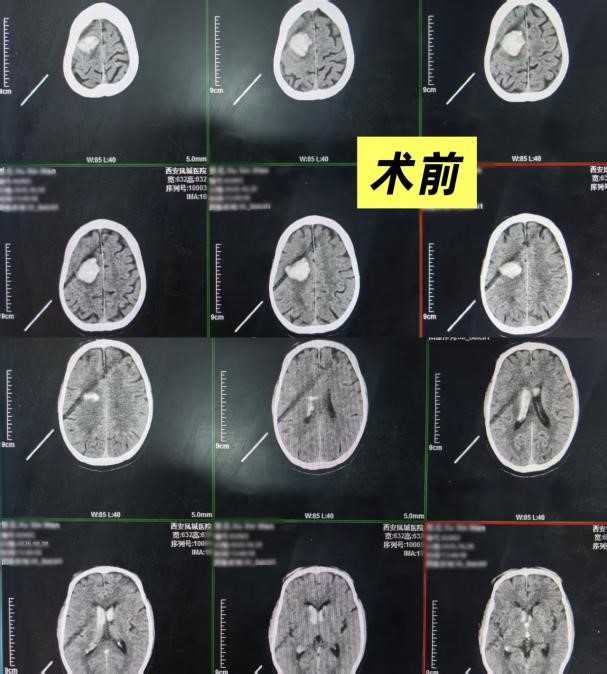

10月31日,来自山东的游客徐先生在我市旅游期间突发急症,被紧急送至西安凤城医院。经诊断,为右侧半卵圆中心脑出血并破入脑室,情况万分危急。来院时,患者已意识嗜睡,左侧肢体完全偏瘫,肌力为0级。生命警报骤然拉响,每一分每一秒都至关重要。

神经外科团队迅速响应,立即为患者开辟脑出血绿色通道。裴宾宾医生及神经外科护理团队凭借丰富的临床经验,在最短时间内为患者实施了颅内钻孔引流术。术中成功清除了血肿,为患者打通了生命的通道。